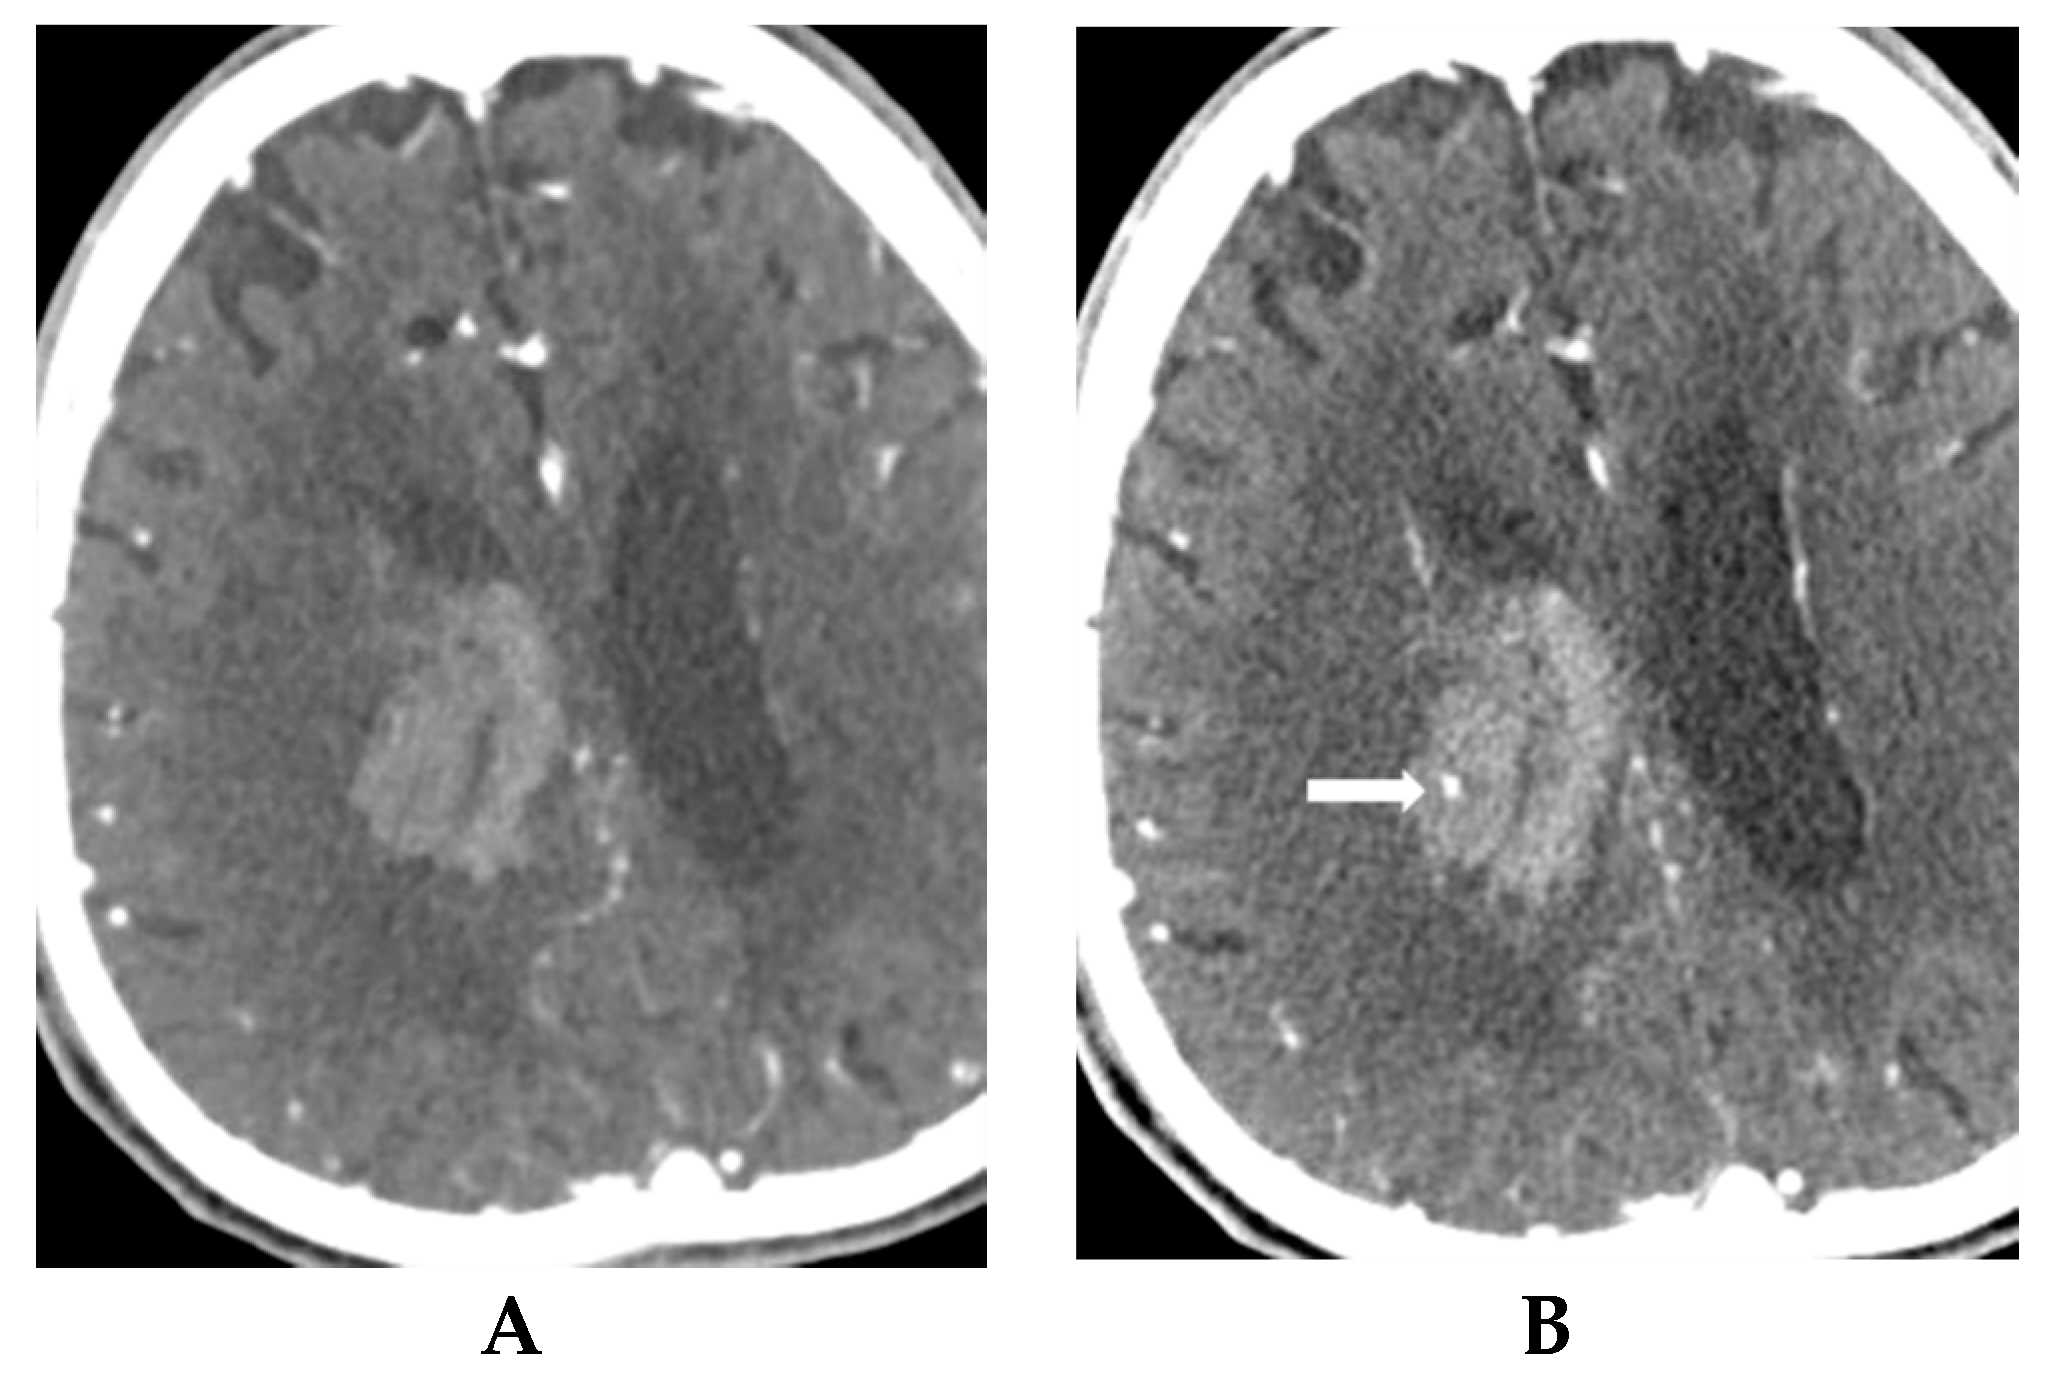

- Park, B.K.; Kwak, H.S.; Chung, G.H.; Hwang, S.B. Diagnostic value of swirl sign on noncontrast computed tomography and spot sign on computed tomographic angiography to predict intracranial hemorrhage expansion. Clin. Neurol. Neurosurg. 2019, 182, 130–135. [Google Scholar] [CrossRef]

- Sporns, P.B.; Kemmling, A.; Schwake, M.; Minnerup, J.; Nawabi, J.; Broocks, G.; Wildgruber, M.; Fiehler, J.; Heindel, W.; Hanning, U. Triage of 5 Noncontrast Computed Tomography Markers and Spot Sign for Outcome Prediction After Intracerebral Hemorrhage. Stroke 2018, 49, 2317–2322. [Google Scholar] [CrossRef]

- Sporns, P.B.; Schwake, M.; Kemmling, A.; Minnerup, J.; Schwindt, W.; Niederstadt, T.; Schmidt, R.; Hanning, U. Comparison of Spot Sign, Blend Sign and Black Hole Sign for Outcome Prediction in Patients with Intracerebral Hemorrhage. J. Stroke 2017, 19, 333–339. [Google Scholar] [CrossRef] [PubMed]

- Sporns, P.B.; Schwake, M.; Schmidt, R.; Kemmling, A.; Minnerup, J.; Schwindt, W.; Cnyrim, C.; Zoubi, T.; Heindel, W.; Niederstadt, T.; et al. Computed Tomographic Blend Sign Is Associated With Computed Tomographic Angiography Spot Sign and Predicts Secondary Neurological Deterioration After Intracerebral Hemorrhage. Stroke 2017, 48, 131–135. [Google Scholar] [CrossRef] [PubMed]

- Rodriguez-Luna, D.; Coscojuela, P.; Rodriguez-Villatoro, N.; Juega, J.M.; Boned, S.; Muchada, M.; Pagola, J.; Rubiera, M.; Ribo, M.; Tomasello, A.; et al. Multiphase CT Angiography Improves Prediction of Intracerebral Hemorrhage Expansion. Radiology 2017, 285, 932–940. [Google Scholar] [CrossRef] [PubMed]